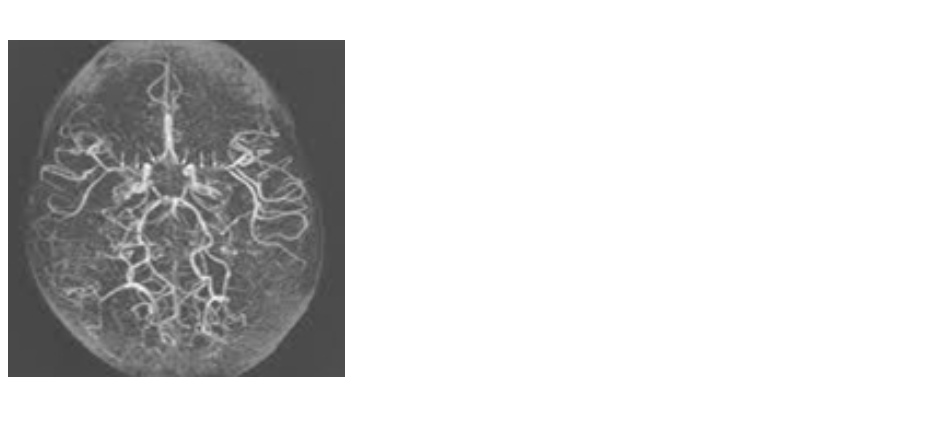

이를 보완하기 위해 형성된 가느다란 신생 혈관들이 연기처럼 보이는 특징적인 뇌혈관 질환입니다.

‘모야모야’는 일본어로 ‘아지랑이처럼 뿌연 상태’를 의미하며, 영상 촬영 시 보이는 혈관 모양에서 유래됐다는 것을 알 수 있어요.

서울아산병원

서울아산병원 좁아지는 혈관은 보통 뇌 기저부(Willis 환)에 위치하며,

보통은 다음과 같은 검사를 진행해요.• MRI, MRA (자기공명영상/혈관조영)

뇌혈류 상태를 확인하고 혈관이 좁아진 부위와 신생 혈관 여부를 확인• SPECT 검사